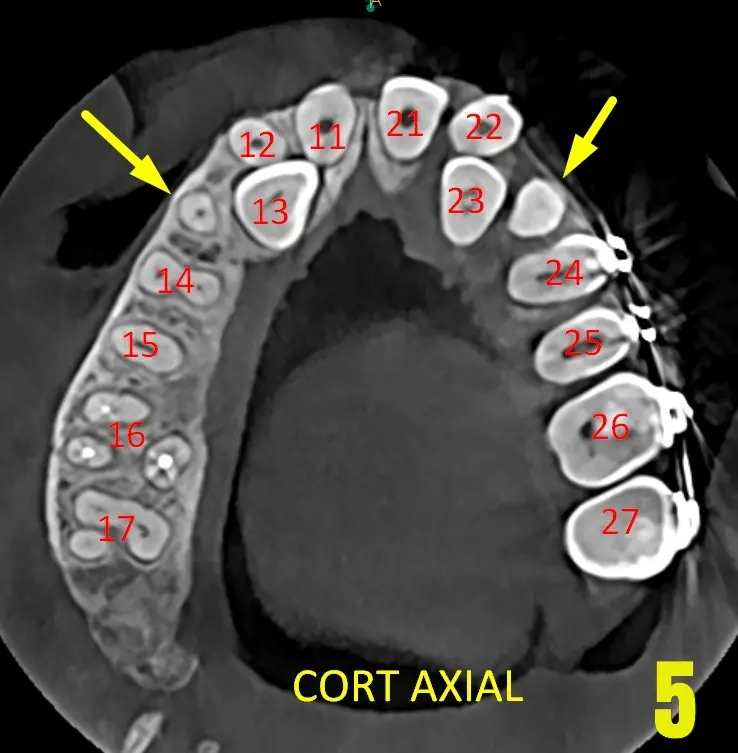

Dientes supernumerarios en zona de piezas dentales 13 y 23, a su vez, se observa ectopia canina bilateral por palatino, ya que el lugar se encuentra ocupado por las piezas supernumerarias. (Imagen 04 y 05). Los cuales se describen con la letra "N" contabilizando 3 en total en el maxilar inferior y ocupando lugares para la normal erupcion de los caninos superiores

Ectopia canina bilateral con desplazamiento hacia la vertiente palatina: La trayectoria eruptiva de las piezas 13 y 2.3 se encuentra alterada, presentando una posición transalveolar oblicua. Esta condición está directamente asociada a la presencia de un elemento supernumerario en la línea media, el cual actúa como una barrera mecánica que impide el descenso fisiológico de los caninos hacia el arco dental.